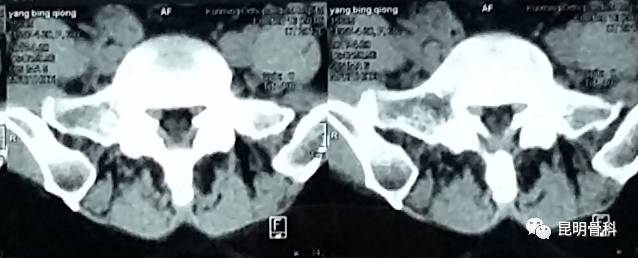

▲光学影像资料显示腰椎间盘突出▼

经多方打听之后,她慕名求助昆明骨科医院。通过诊断后,赵女士被确诊为“腰4-5椎间盘突出。”骨病科张鑫主任在仔细研究了腰椎CT及核磁共振片后,结合病情实事求是地告诉她,椎间盘突出比较严重,且还有椎管狭窄、侧隐窝狭窄等,已经明显压迫到神经。现在用保守治疗已无效果,只有把压在神经上的椎间盘取出来,才能从根本上解决问题,而昆骨微创/椎间孔镜就是较好的选择。